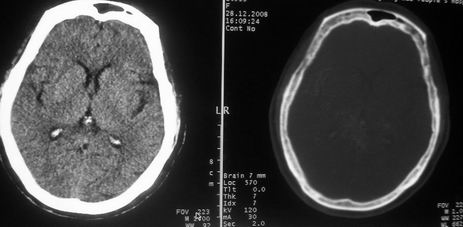

女,72岁,头晕。额骨有无问题。

额骨呈磨玻璃状增厚,考虑骨纤。

额骨呈磨玻璃状增厚,考虑骨纤

骨纤维组织异常增殖症又名纤维性骨炎,是一种以骨纤维变性为特点的骨胳系统疾病,是否为一真性肿瘤尚无定论。该病好友于儿童及青年,女性较多见,60%发生于20岁以前,偶见于婴儿和70岁以上老年人。男女发病为1∶2。80%以上表现为病骨区畸形肿胀;建议祥问病史,时间?